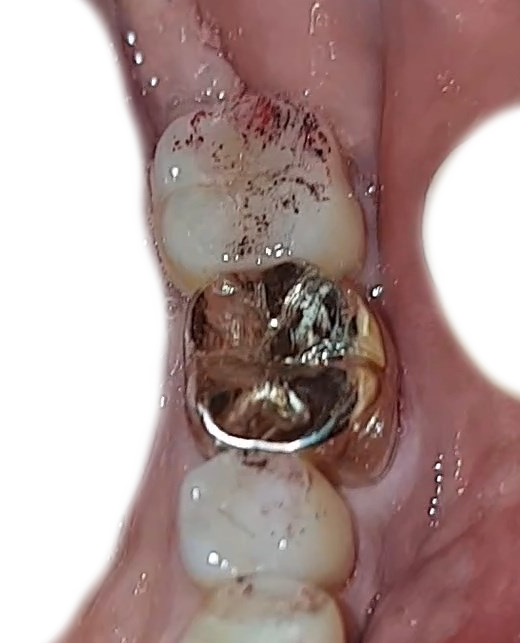

자...이제..금이빨 결과를 볼 차례다.

살작 비위가 상할 수 있는 것이라..마지막에 올린다.

금이빨 하고난 뒤 느낌?

혀가 금이빨에 닫을때마다...미끌 거리면서...나쁘지 않다..

키스하는 느낌? ㅋㅋㅋㅋㅋㅋㅋㅋㅋ

금이빨을 끼우고 빼고 하면서..

무엇인가 계속 체크하고 테스트하면서..

무엇인가를 물고 이로 짓이기고 하는데...그것이 잉크가 묻어있는 성분인가?

이빨에 뭔 검은 찌꺼기들이 또...보인다.

여하튼...아래의 이미지가 최종 결과니..

궁금하신 분들은

쫌...더러워도..궁금하다면?..

봐라!!